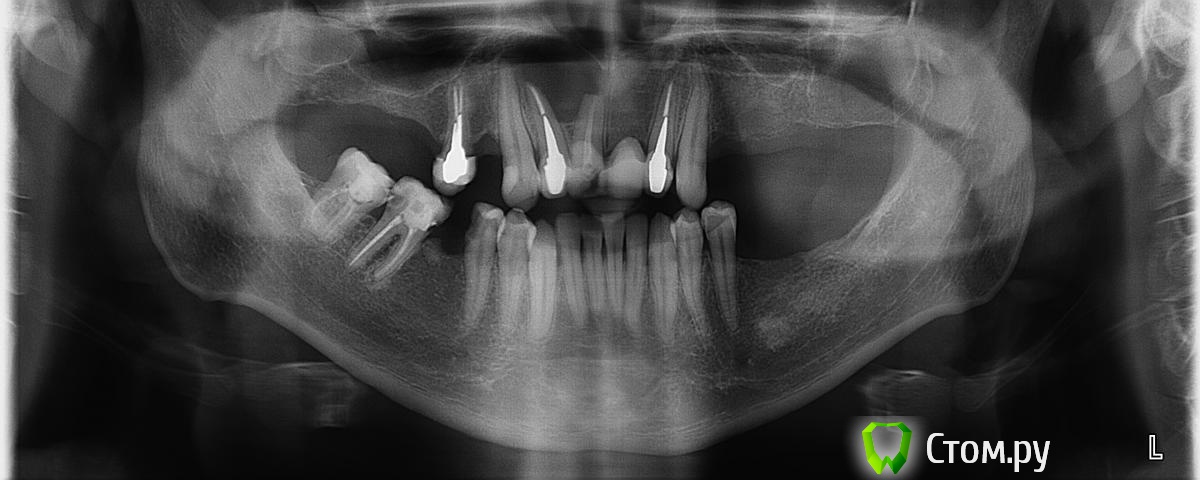

negodyai Опубликовано 17 октября, 2014 Поделиться Опубликовано 17 октября, 2014 Добрый день! Подскажите пожалуйста по моей ситуации. Свежего снимка к сожалению не нашел. Думаю, специалистам будет понятно, снимок сделан ДО цистэктомии передних зубов или после :-\ Летом заниматься зубами не было финансовой возможности. Сейчас созрел.Что посоветуете? В ближайшей клинике, после операции по удалению кисты, мне посоветовали ставить брекеты на нижнюю челюсть, для выравнивания прикуса, затем, возможно нужен будет синус-лифтинг верхней челюсти (на месте удаления кисты "пустота") с подсадкой костной ткани, затем, одномоментная имплантация, 6-7 имплантатов на мостах.. Речь шла о имплантатах какой-то корейской фирмы, насколько они хорошие и что за фирма, не сказали.Нуждаюсь в вашем совете. Ссылка на комментарий

negodyai Опубликовано 17 октября, 2014 Автор Поделиться Опубликовано 17 октября, 2014 Все примерно так.. я бы сделал кт снимок КТ есть, просто на диске, нет возможности выложить. Все что сказали в клинике, основано на снимках и КТ, конечно... Цистэктомию единицы делали. Клык не смотрели ? Там киста большая была, причем рецидив. Первый раз сделал в гос. поликлинике, что-то там не доделали и она снова выросла, уже в этот огромный размер. Клык хотели удалять вначале, но вроде обошлось... Сейчас новые снимки сделать нужно, надеюсь, все нормально там будет на этом месте... Я что спросить хотел, в Белорусь имеет смысл ехать протезироваться? Я так понял, имплантаты вроде Штраумана или Нобеля, Ксайта, там не сертифицированы, в основном MIS они практикуют... Ссылка на комментарий